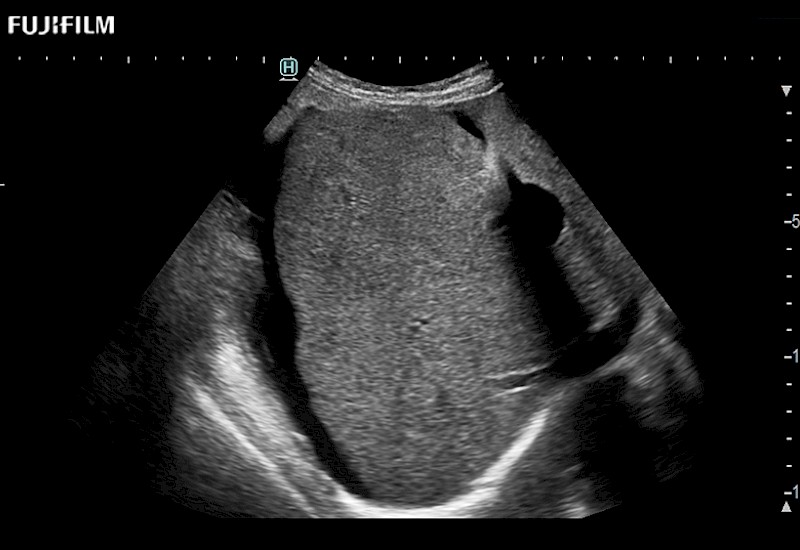

The ARIETTA 650 DI combines trusted Fujifilm Healthcare technologies and features tailored for surgical oncology.

Designed to meet the demands of surgeons, the ARIETTA 650 DI offers precise guidance. Its advanced capabilities and large, intuitive display offer accurate and efficient care in operating rooms and specialized surgical settings.